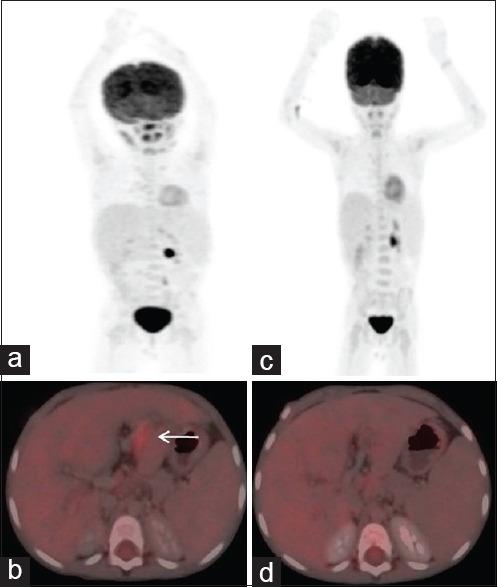

Role of FDG PET/CT in evaluation of biliary tract diseases remains relatively unexplored. PET/CT with FDG helps in evaluation of both infective / inflammatory as well as neoplastic diseases as increased glucose utilization is observed in both the conditions. In this article, we describe the spectrum of FDG PET/CT findings in various diseases affecting the biliary tract. Role of FDG PET/CT in neoplastic diseases involving the biliary duct has been described at the time of staging and response evaluation; in characterization of the intrahepatic mass (abscess v/s cholangiocarcinoma). In addition, we have discussed about the false positive FDG uptake along the biliary duct stent, which interfere with scan interpretation. Few of the benign conditions described are Langerhans cell histiocytosis and IgG4 related disease involving the biliary duct and adenomyomatosis and Xanthogranulomatous cholecystitis involving the gall bladder.

氟代脱氧葡萄糖正电子发射断层显像/计算机断层扫描(FDG PET/CT)在胆道疾病评估中的作用仍相对未被充分探索。含氟代脱氧葡萄糖的PET/CT有助于评估感染性/炎症性疾病以及肿瘤性疾病,因为在这两种情况下均观察到葡萄糖利用率增加。在本文中,我们描述了FDG PET/CT在影响胆道的各种疾病中的表现谱。FDG PET/CT在胆管肿瘤性疾病分期和疗效评估以及肝内肿块(脓肿与胆管癌)鉴别诊断中的作用已被阐述。此外,我们还讨论了沿胆管支架出现的FDG摄取假阳性情况,这会干扰扫描结果的解读。所描述的一些良性疾病包括累及胆管的朗格汉斯细胞组织细胞增多症和IgG4相关疾病,以及累及胆囊的腺肌增生症和黄色肉芽肿性胆囊炎。